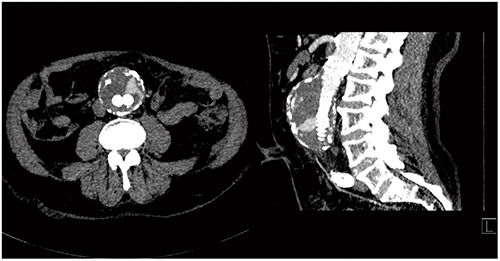

Case8は左総腸骨動脈の閉塞症例であるが,大規模なバイパス術の適応となるのか,総腸骨動脈のみの血管再建術の適応となるのかを,4D CTAにて容易に判断できる(図13)。

図13 Case8:左総腸骨動脈完全閉塞症例

4D CTAはステントの評価にも有用である。Case9はステント内狭窄疑いの症例である。シネモードで時系列画像を詳しく見ると,側副動脈およびステントの血行動態的に著明な狭窄がないことが明確にわかる(図14)。

図14 Case9:ステント内狭窄疑い症例の4D CTA画像